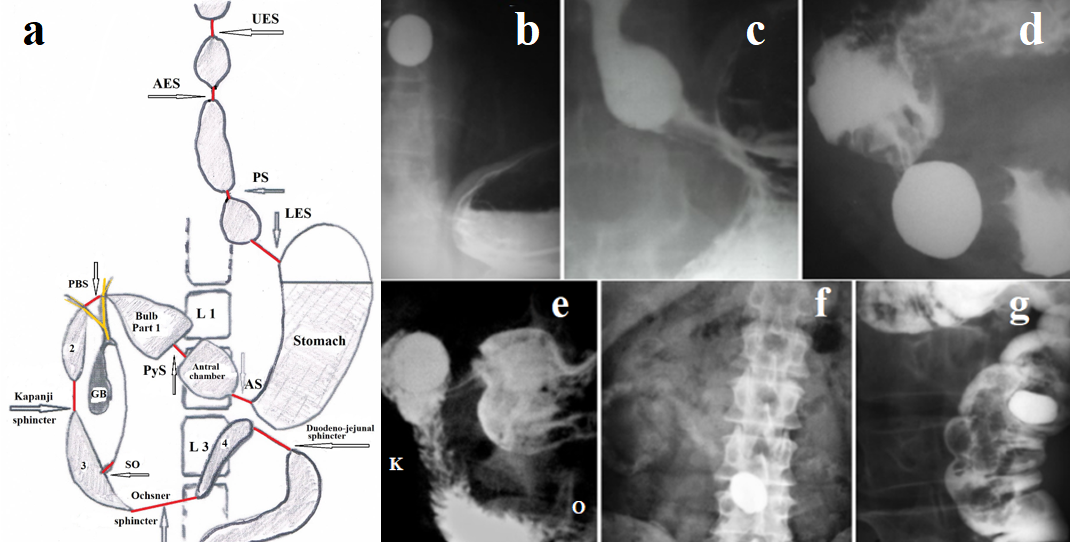

Based on the regularity of the motor function of the esophagus, which states that the movement of the bolus in the digestive tract occurs in the cranio-caudal direction because of the peristaltic wave, I perform dilation of all sphincters by offering patients with GERD to drink a dense large tablet (LT) with a diameter of 1.9 cm or 2.3 cm. The tablet is made from equal parts of flour and barium sulfate, dried and covered with a thin layer of a substance that enhances sliding in the oropharynx. The tablet is swallowed on an empty stomach and washed down with water. If the patient feels that the tablet is stuck in the esophagus, it is enough to swallow a piece of bread to push the tablet down. The tablet passes through the entire digestive tract, stretching all narrow segments, including the sphincters. Its movement is not felt by the patient, and it does not damage the tissues of the digestive system. In the process of moving through the digestive tract, the surface layers of LT dissolve and the tablet decreases in size. Therefore, it cannot get stuck in the intestine. All sphincters of the upper gastrointestinal tract are shown in Figure 3a & Figure 3b-3g shows radiographs at different stages of the LT movement through the intestine.

Figure 3. (a). Scheme of the sphincters of the upper gastrointestinal tract (length is shown in brackets). UES-upper esophageal sphincter; AES – aorto-esophageal sphincter; PS – proximal sphincter (0.5-0.7 cm); LES -lower esophageal sphincter (≈ 4 cm); AS – antral sphincter; PyS – pyloric sphincter (≈0.5-1.0 cm); PBS – postbulbar sphincter; Kapanji sphincter (2.05±0.09 cm); SO – sphincter Oddi (≈ 1cm); Ochsner sphincter – (3.2±0.15 cm); duodeno-jejunal sphincter (1.6±0.04 cm). (b-g). LT passed through UES (b); it is before LES (c); in antral chamber (d); in duodenal bulb (e); in small intestine (f); in descending colon.

The LT passes through all the sphincters, stretching them and improving their patency. The exception is the SO, as the tablet passes by to it. However, as can be seen in Figure 8e, the tablet is on its way through the Kapandji (K) and Ochsner (O) sphincters, because of which the pressure in the chamber between these sphincters, where the SO opens, decreases. This facilitates the outflow of bile and pancreatic juice. As the tablet moves through the small intestine, the surface layer of the tablet dissolves, and it decreases in size. In Figure 3f, barium “clouds” are visible in the small intestine, and the diameter of the tablet is noticeably smaller than in the previous stages.